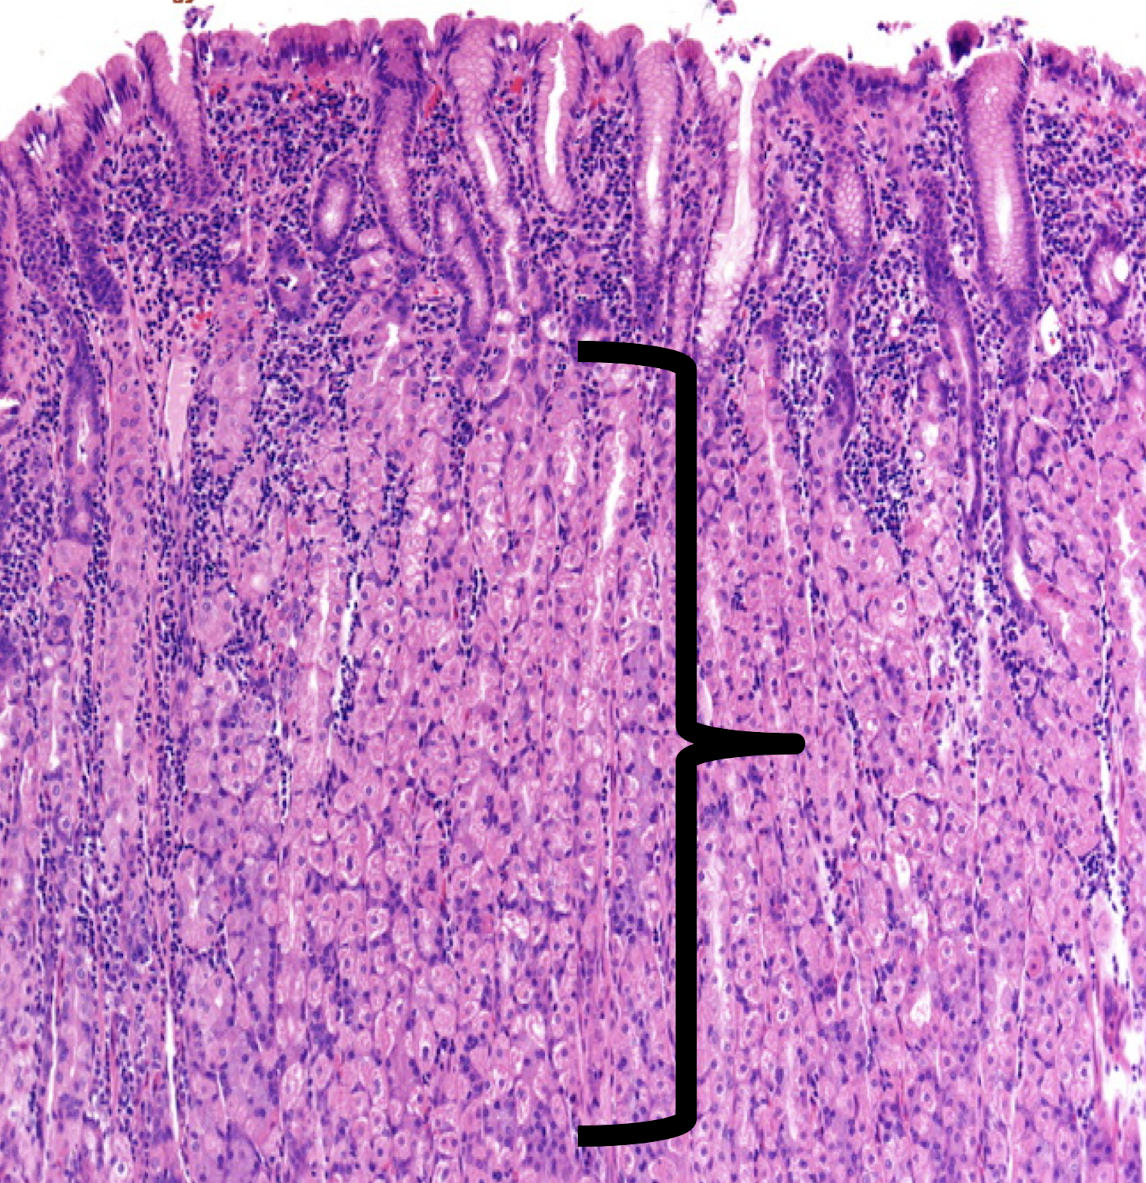

JEJUNUM

prominent plicae circularis

increase surface area = increase absorption

Identify the structure and its characteristic feature

A: mucosa

B: submucosa

C: tunica muscularis

D: tunica serosa

Identify the structure